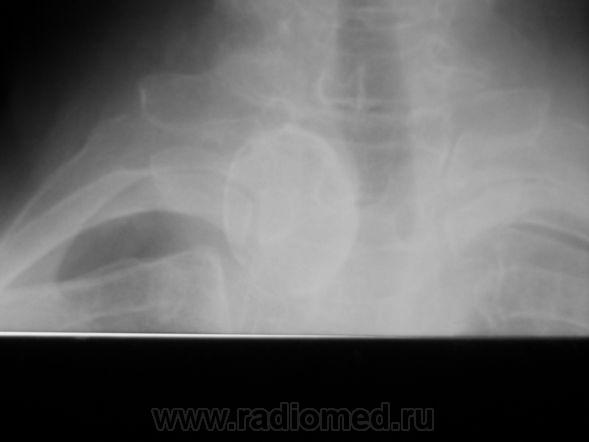

Пол пациента: Женский пол Тип патологии: Доброкачественное новообразование, киста Область исследования: Челюстно-лицевая область и шея Методы исследования: Rg https://radiomed.ru/sites/default/files/styles/case_slider_image/public/user/1787/P1010362.JPG?itok=_9pgk0if https://radiomed.ru/sites/default/files/styles/case_slider_image/public/user/1787/P1010361.JPG?itok=4DBcALkX ID:2683 Пт, 09/04/2010 - 14:55 #1 Ola-la Не на сайте Был на сайте: 10 месяцев 3 дня назад Зарегистрирован: 06.12.2008 - 09:33 Публикации: 1786 Думаю, это обызвествление в щитовидной железе. https://www.instagram.com/pediatricradiology/ Сб, 10/04/2010 - 19:52 #2 арнольд Не на сайте Был на сайте: 1 год 11 месяцев назад Зарегистрирован: 22.12.2008 - 16:50 Публикации: 196 Возможно это родимое пятно на коже. Сколько лет человеку? Dat.Dicat.Dedicat. Сб, 10/04/2010 - 21:44 #3 Петрович Не на сайте Был на сайте: 7 лет 2 месяцев назад Зарегистрирован: 22.03.2009 - 01:13 Публикации: 3908 арнольд wrote: Возможно это родимое пятно на коже. Сколько лет человеку? . Родимое пятно не должно смещать трахею. В любом возрасте. Неоднозначно всё Вс, 11/04/2010 - 15:19 #4 stovbav Не на сайте Был на сайте: 2 года 2 месяцев назад Зарегистрирован: 20.12.2009 - 17:28 Публикации: 7066 Как жалко, что на боковом только чуть верхнего края захвачено...получили бы массу дополнительных эмоций (информации я имел ввиду), по поводу обызествленного узла щитовидки согласен на все сто!!!!!!!!!! Болезни ног: виды, симптомы, причины, профилактика и лечение Пнд, 12/04/2010 - 11:03 #5 Vikkur Не на сайте Был на сайте: 4 года 7 месяцев назад Зарегистрирован: 24.09.2009 - 14:34 Публикации: 1749 Да киста)) Нашел сегодня данные УЗИ. ))) Виктор.

Думаю, это обызвествление в щитовидной железе.

Родимое пятно не должно смещать трахею. В любом возрасте.

Как жалко, что на боковом только чуть верхнего края захвачено...получили бы массу дополнительных эмоций (информации я имел ввиду), по поводу обызествленного узла щитовидки согласен на все сто!!!!!!!!!!

Да киста)) Нашел сегодня данные УЗИ. )))